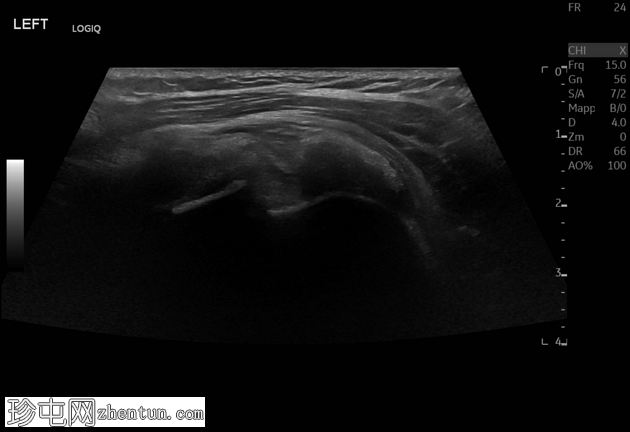

超声

肩峰下滑囊-三角肌下滑囊积液内可见轻度高回声、不均匀的钙化灶,无声影(“浆液状钙化”)。滑囊壁增厚,周围脂肪间隙水肿。